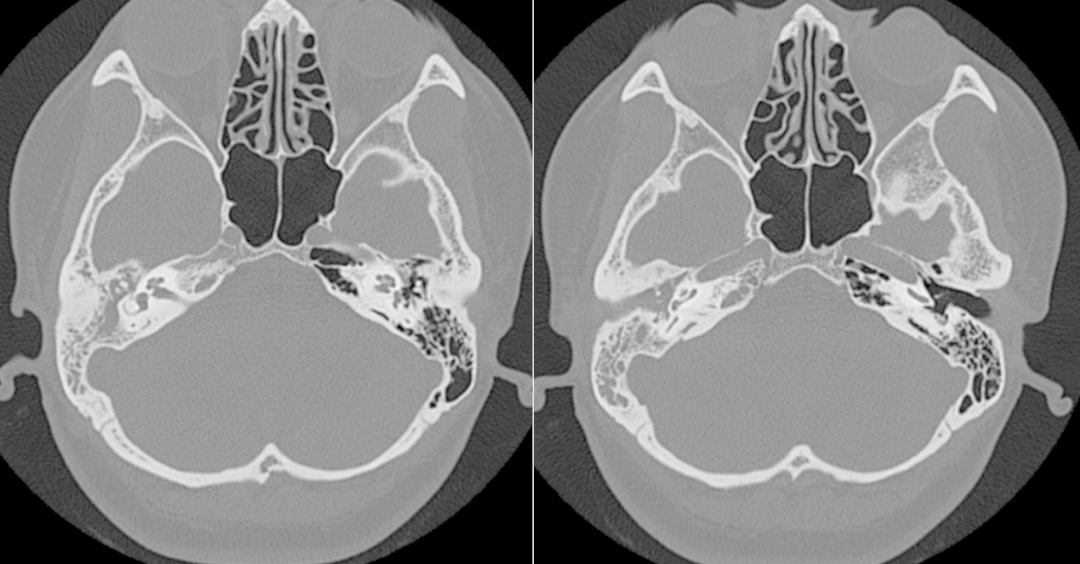

术前CT

由于患者属于二次手术,正常的解剖结构遭到了破坏、长期的炎症病变使术区不断渗血且粘连明显极大地加大了手术难度。在团队的配合下,张晓彤教授凭借着高超的医术克服手术中的重重困难,经过近4小时的紧张奋战,手术顺利完成。术后,在医护人员的精心照料下,李女士恢复良好。